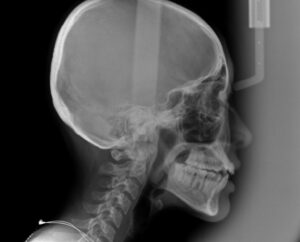

出っ歯でないか

確認のレントゲンを撮影

歯科医が分析した結果

今回は小臼歯の抜歯は不用